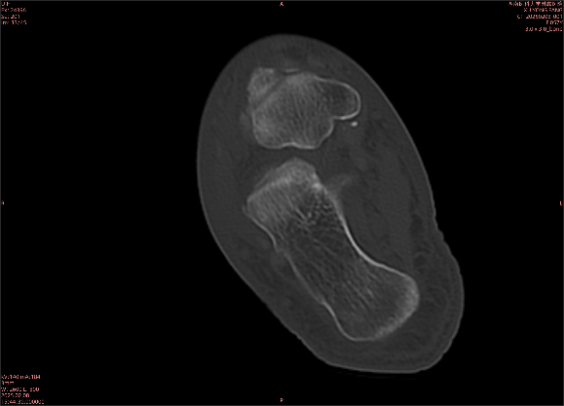

舉例圖像

圖1

專(zhuān)業(yè)解釋看不懂沒(méi)關(guān)系,大家看圖1和圖2就可以了,這是同一個(gè)患者跟骨的磁共振和CT圖像,圖1的紅色箭頭指示的黑線就是磁共振圖像顯示的骨折線,一目了然。而對(duì)比圖2的CT圖像上并未顯示異常。